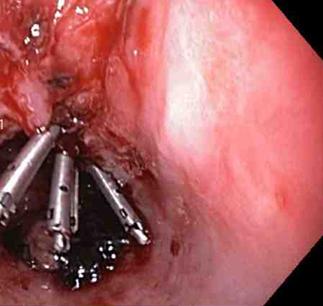

Three through-the-scope clips deployed to complete closure of the mucosal defect

From the collection of Juan Carlos Munoz, MD, University of Florida